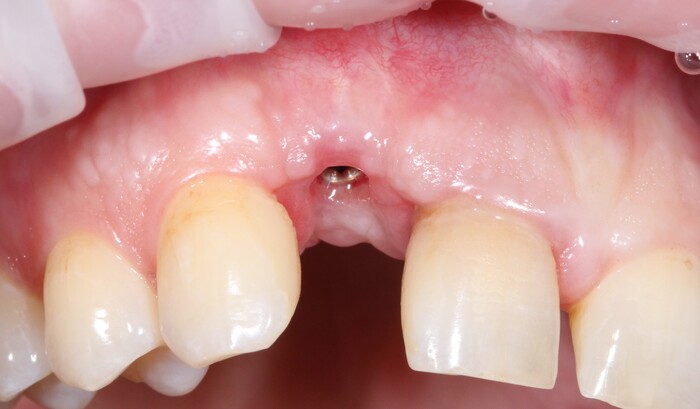

После снятия коронки:

Выкрутили абатмент:

Установлена заглушка, которая закрывает шахту имплантата.

Теперь необходимо выждать около 2-х месяцев для того, чтобы десна восстановилась (Пациентка это время ходила со специальной капой, которая имитирует наличие зуба).